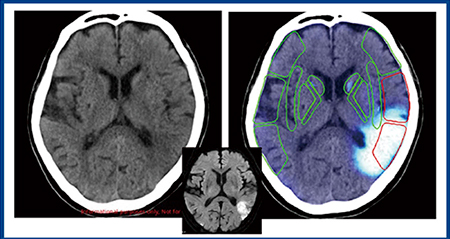

図3は,計算ができない,左右がわからないという主訴で来院した症例である。専門医ならば,左のMCA領域に梗塞を疑うが,非専門医では読み取るのが難しいと思われる。Ischemia analysisでは,虚血をピックアップして,CT-ASPECTSにより虚血があるエリア(減点)を赤枠で示し点数を自動計算する。また,図4では,右の大脳半球に広範な低吸収域が認められるが,Ischemia analysisの虚血サインは左のM5,M6領域を指している。右の低吸収域は古い梗塞巣と判断され,陳旧性病巣は除外できるのもポイントである。

図4 Ischemia analysisのCT-ASPECTS自動計算2